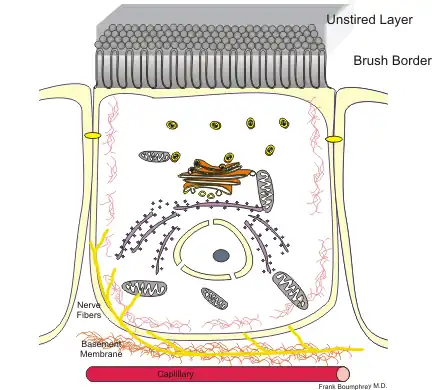

Transport Epithelia

These epithelia are found lining the tubes of the intestine and the kidney.

- The cells are usually columnar and regulate the exchange of nutrients an ions.

- The apical surface usually has microvilli, fingerlike projections that can increase the absorptive area up to 100X.

- These cells are usually bound together with tight junctions

- These cells usually have a high metabolism (numerous mitochondria)